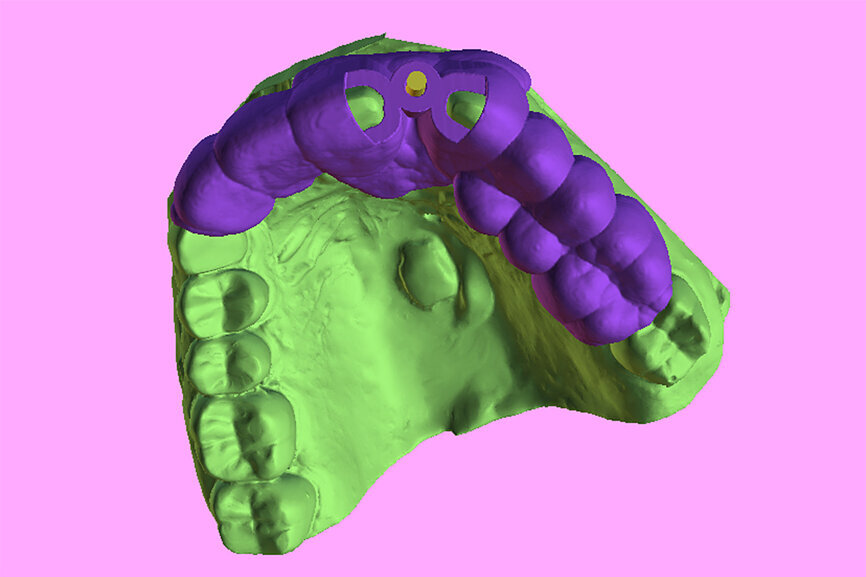

Fig. 6a: Two 3D-printed templates designed on the digitised model (green): one for the initial drill to section the tooth at the root apex (a) and the second for using sequential guided drills to drill through the root itself (b).

Fig. 6b: Two 3D-printed templates designed on the digitised model (green): one for the initial drill to section the tooth at the root apex (a) and the second for using sequential guided drills to drill through the root itself (b).

Planning with such precision is predicated on the acquisition of a satisfactory CBCT scan with a proper field of view and the incorporation of occlusal surface data STL files of the arch form, digitised through either an intra-oral scan or a desktop scanner imported into the software. Two 3D-printed templates were then designed on the accurate digitised surface model, one for the initial drill to section the tooth at the root apex and the second to use sequential guided drills to drill through the root itself (Fig. 6).